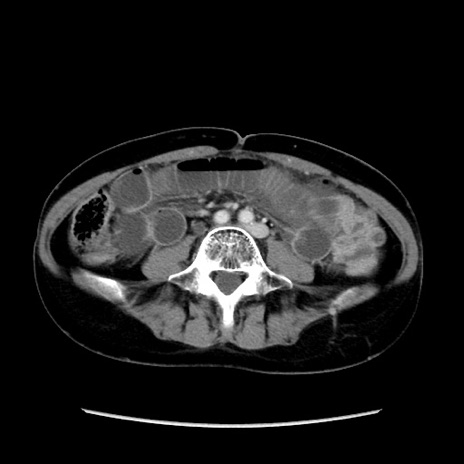

症例32(横断像)

【症例】40歳代 女性

【主訴】上腹部痛、嘔気・嘔吐

【現病歴】約9時間前頃から急に上腹部痛、嘔気、嘔吐が出現。改善しないため救急要請。

【既往歴】子宮頚癌(広汎子宮全摘術、放射線療法)、腸閉塞

【身体所見】腹部:平坦、軟、腸雑音亢進、上腹部を中心に腹部全体に圧痛あり。

【データ】WBC 8400、CRP 0.03